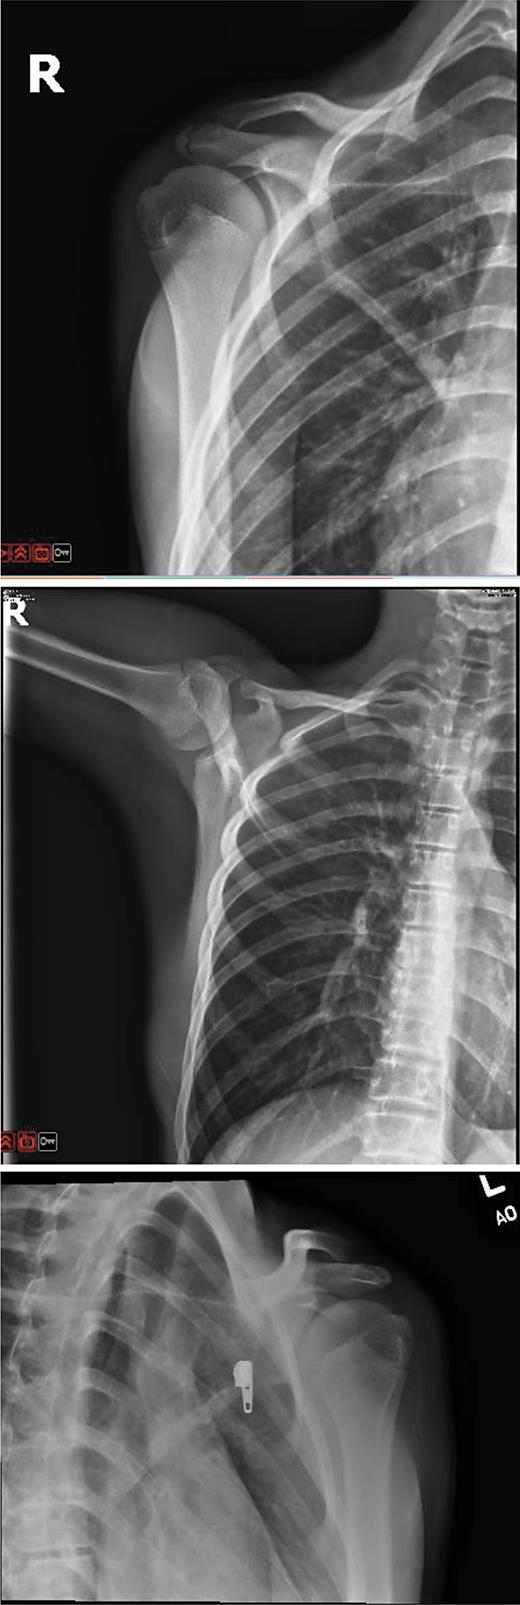

Conventional radiographs of the shoulder. (A) Anteroposterior (AP) view X Ray Shoulder Grashey Learn about the conventional radiography views of the shoulder, including the grashey view, which is a tangential view of the. For many patients with chronic shoulder pain, the typical recommended views are ap internal rotation, grashey or a second ap view with external rotation, and axillary views. Normal ap oblique internal rotation view (grashey view). Learn about the different views. X Ray Shoulder Grashey.

Bilateral Acromioclavicular Joint Subluxation in an Adolescent with X Ray Shoulder Grashey Learn about the different views and techniques for shoulder radiographs and mri, including the humerus xray. A radiographic projection of the shoulder joint to assess the glenoid rim, the humerus and the joint space. Learn about the conventional radiography views of the shoulder, including the grashey view, which is a tangential view of the. Learn how to obtain and interpret. X Ray Shoulder Grashey.